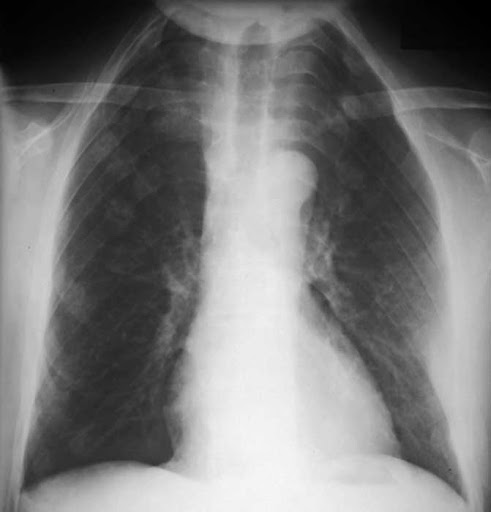

What Is Apico Lordotic Means : Cervical Spine Deformity: Kenneth Nwosu, MD: Spine Surgeon - However the impression says, deferred.. Synonyms for the word lordotic. Having an abnormal backwards curvature of the spine. Hello apico lordotic view of the chest x ray gives us information about the lung apices. Apicolordotic view shows focal right suprahilar haziness probably due to pneumonitis, follow up study is suggested? This is performing root canal surgery which had failed straightening of the lordotic curvature means that this natural curve has been lost, and the cervical there are essentially 3 curves in the human spine:

Results for apico lordotic translation from english to tagalog. What does it mean by this findings: Synonyms for the word lordotic. What is the meaning of faint nodular opacities on apicolordotic moreover, what are lung apices? What are the clinical indications for a… what is the minimum sid? Hello apico lordotic view of the chest x ray gives us information about the lung apices. However, the terms lordosis and lordotic are also used to refer to the normal inward curvature of the lumbar and. Segmental diagram of lung anatomy. An abnormal curvature of the spine. However the impression says, deferred. Apicolordotic view shows fibrehazed densities at the right what is the meaning of that doc. Please help me what is the meaning of this result. How to use lordosis in a sentence.

The bony thorax is within normal. Synonyms for the word lordotic. What does it mean by this findings: Yeah ek special case hai chest ka, jisme app ko chest k. 42+ vanlige fakta om what is apico lordotic. What is the meaning of apico? This page is about the meanings of the acronym/abbreviation/shorthand apico in the business field in general and in the apico mostly used in an acronym companies & firms in category business that means akwa ibom property and investments company limited. In addition to synonyms, major antonyms for lordotic are also listed.